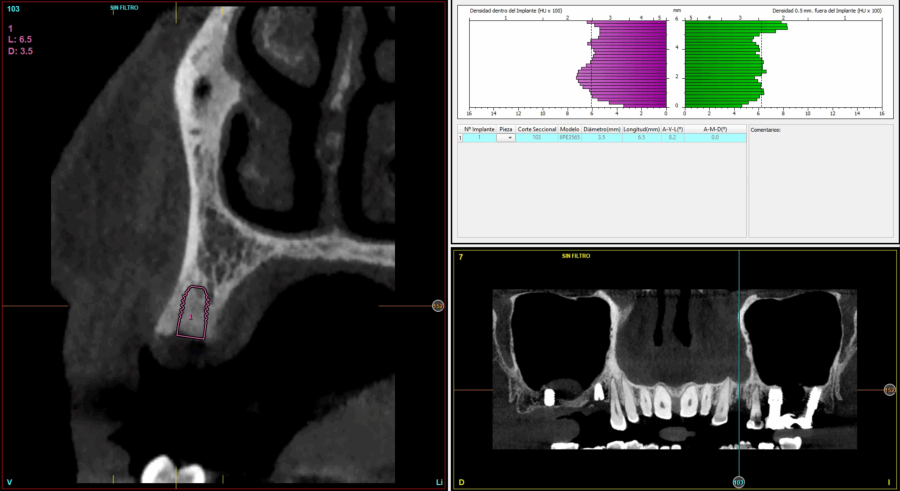

Todas las cirugías fueron realizadas por un único cirujano bajo anestesia local, tras un diagnóstico previo del lecho óseo mediante tomografía volumétrica (CBCT) procesada con un software específico de planificación implantológica (BTI-Scan III). La preparación del lecho implantario se llevó a cabo siguiendo la técnica de fresado biológico a bajas revoluciones descrita por Anitua y cols.19.

En cuanto a la rehabilitación protésica, en todos los casos se utilizó una prótesis atornillada con transepitelial para prótesis unitaria. La supervivencia de las prótesis fue del 100%, sin encontrarse fracaso en ninguna de ellas al igual que los implantes, con un tiempo de seguimiento de tres años. Durante el primer año, en las visitas de control, ninguno de los implantes mostró sangrado al sondaje ni inflamación de los tejidos periimplantarios. La media de la pérdida ósea en este punto fue de 0,32 mm (+/- 0,60) y la media de la pérdida ósea distal de 0,31 (+/- 0,48). A los dos años, no se registraron tampoco signos inflamatorios en ninguno de los implantes y la pérdida ósea mesial del conjunto fue de media de 0,38 mm (+- 0,54) y la distal de 0,64 mm (+/- 0,70). En la última visita a los 3 años, los tejidos periimplantarios siguieron estables, sin signos de inflamación y la media de la pérdida ósea mesial fue de 0,40 mm (+/- 0,53) y la distal de 0,69 (+/- 0,55) (Figura 5). En las Figuras 6-12 se muestra uno de los casos incluidos en el estudio.